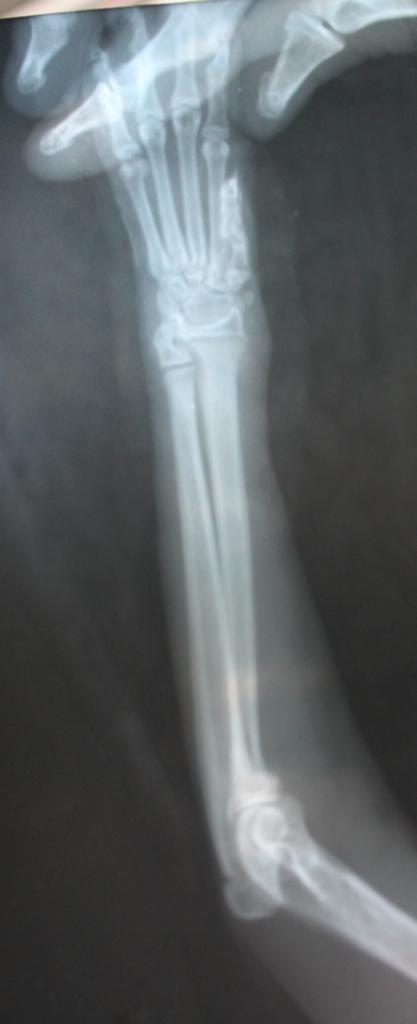

По умолчанию рентген передней лапки котёнка

ID:	3353072 и никаких раздробленных костей не видно, как утверждал врач из Амулета.

О том, что перелома не было и нет, подтвердил и сам ветеринар, к которому я успела заехать после рентгена сегодня вечером.

вот и не лень вам писать всякую чушь... специально увеличила снимок, чтоб лучше было видно... специалистам (если тут они вообще есть), а ни тем, кому что-то кааажется... SHADOW (она же ТЕНЬ), вам в другую тему... https://forumodua.com/showthread.php?t=5412

Вот не задача не продумала такой пустяк... лапка у котенка на снимке то левая, а повреждена то правая...! Хотя тем кто не видел котенка можно же лапшу на уши намотать... да?

Снимки с каким то разным оттенком один черно-белый и четкий а второй мутновато-непонятного цвета.

Просто очень давно у меня палец большой на руке после травмы гнил, загноилась кость в общем история длинная, но одно могу сказать за 6 месяцев что у меня эпопея с пальцем была мне тонну снимков сделали, поэтому на снимки я насмотрелась достаточно. Эти 2 снимка были сделаны на разных рентген аппаратах, это я могу сказать с полной уверенностью!

То что лапа на снимке взрослого кота, а не 3-4 месячного котенка тут я полностью согласна, то что котенок был это факт 100% сама лично видела в клинике, если надо то вспомню дату. С масиком все будет в порядке, ему вовремя помощь оказали